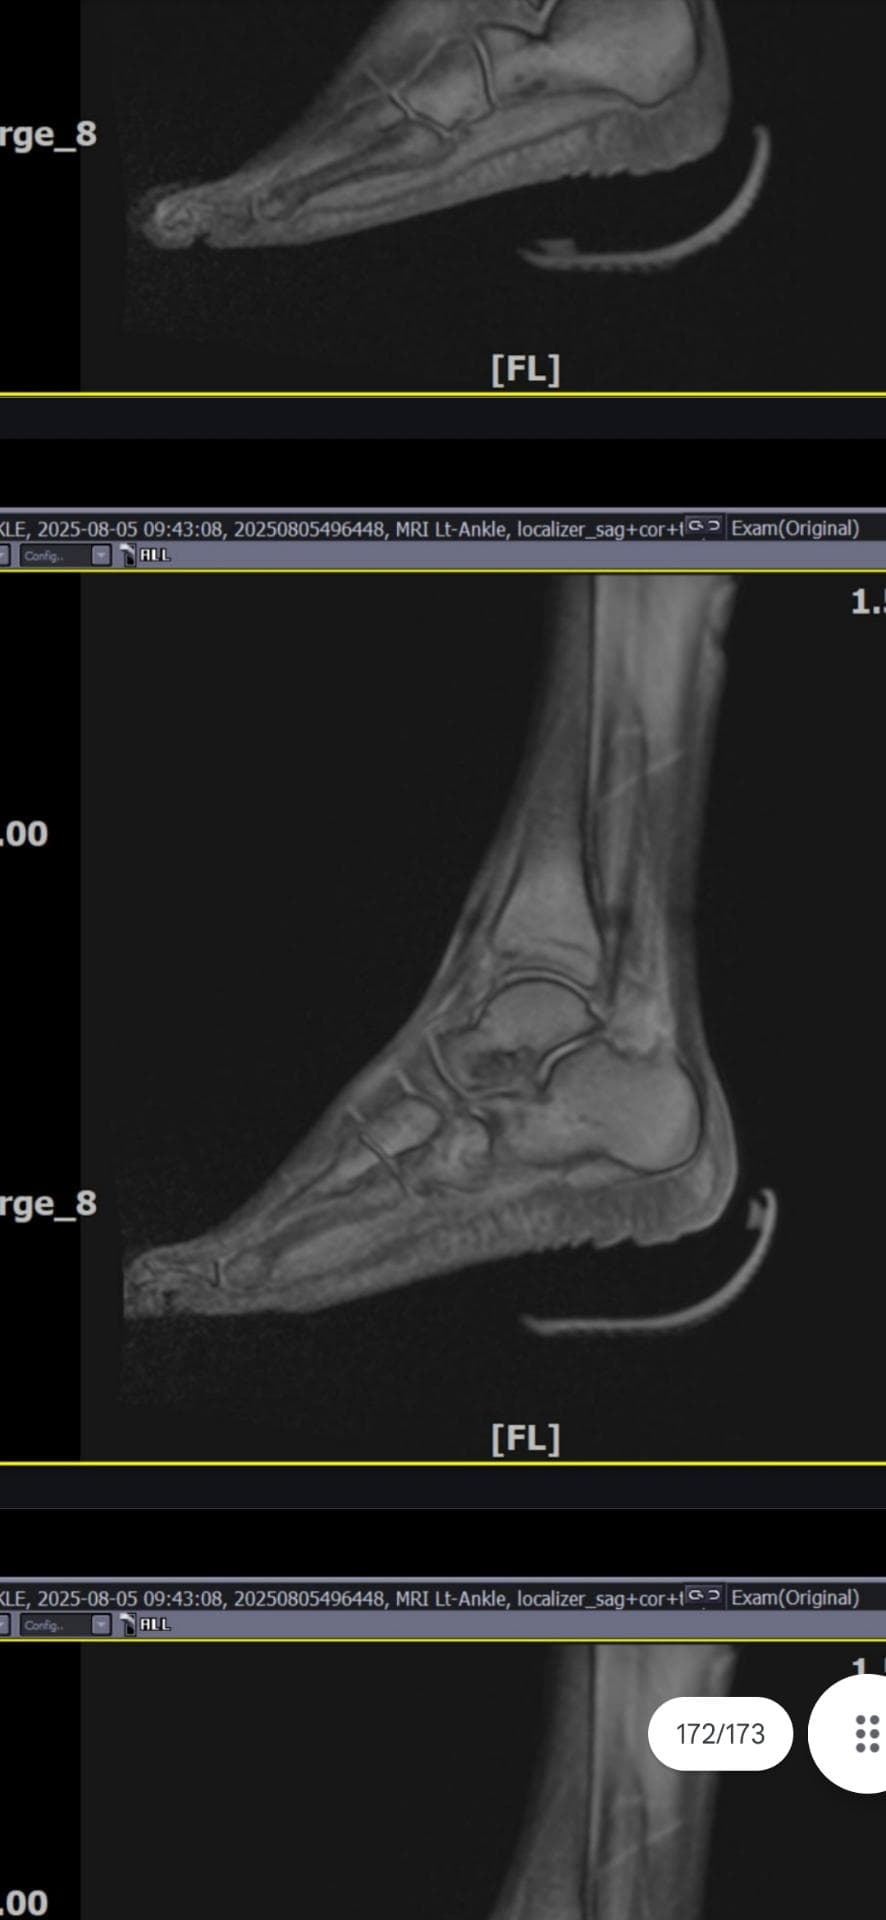

그래도 통증이 남아 8월 5일에 MRI를 촬영했는데, 병원에서는 “인대는 이어져 있고, 이 정도면 재활운동으로 호전될 것”이라는 설명을 들었습니다.

MRI 상 전거비인대와 발목 상태가 정말 회복 단계인지, 아니면 만성으로 넘어가는 건 아닌지 전문가분들의

의견을 듣고 싶습니다.

mri 사진(8월 촬영)상 인대가 호전됬는지도

알고 싶습니다.